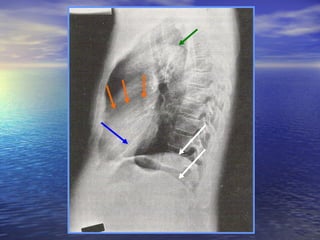

Surface projections of the lungs and the pleural cavities The apex of each lung projects above the medial third of the clavicle. Interlobar fissures The oblique fissure begins posteriorly in the upper thoracic region, crosses the 5th and 6th ribs, curves laterally to the midaxillary  line, and courses along the lower border of the 6 th  rib to the lateral border of the sternum. The right lung's horizontal fissure courses along the lower border of the 4th rib from the midaxillary line to the lateral border of the sternum

Surface projections ofthe lungs and the pleural cavities The apex of each lung projects above the medial third of the clavicle. Interlobar fissures The oblique fissure begins posteriorly in the upper thoracic region, crosses the 5th and 6th ribs, curves laterally to the midaxillary line, and courses along the lower border of the 6 th rib to the lateral border of the sternum. The right lung's horizontal fissure courses along the lower border of the 4th rib from the midaxillary line to the lateral border of the sternum